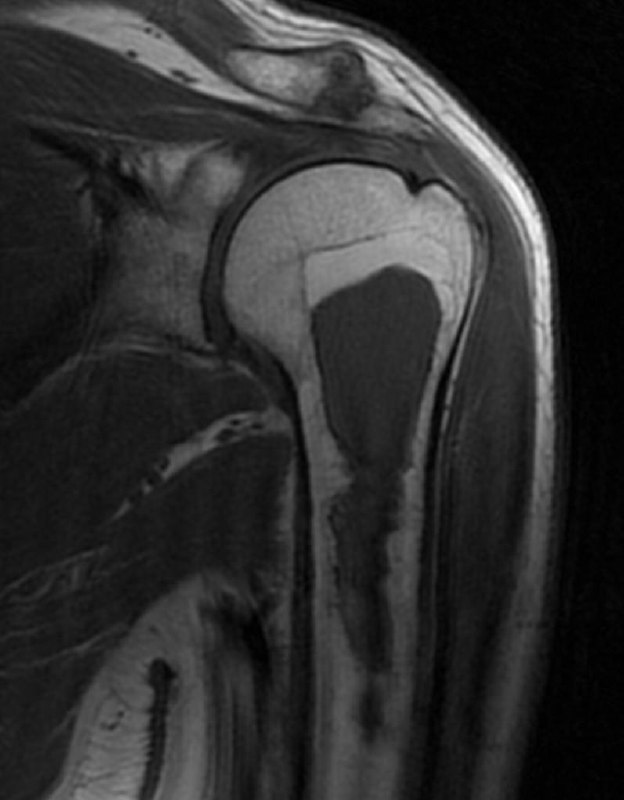

показательный случай острого (хорошо, свежего!) разрыва сухожилия длинной головки бицепса плеча, с приличным диастазом. стрелками указаны края дистального и проксимального фрагментов сухожилия. На последнем снимке - пустая межбугорковая борозда